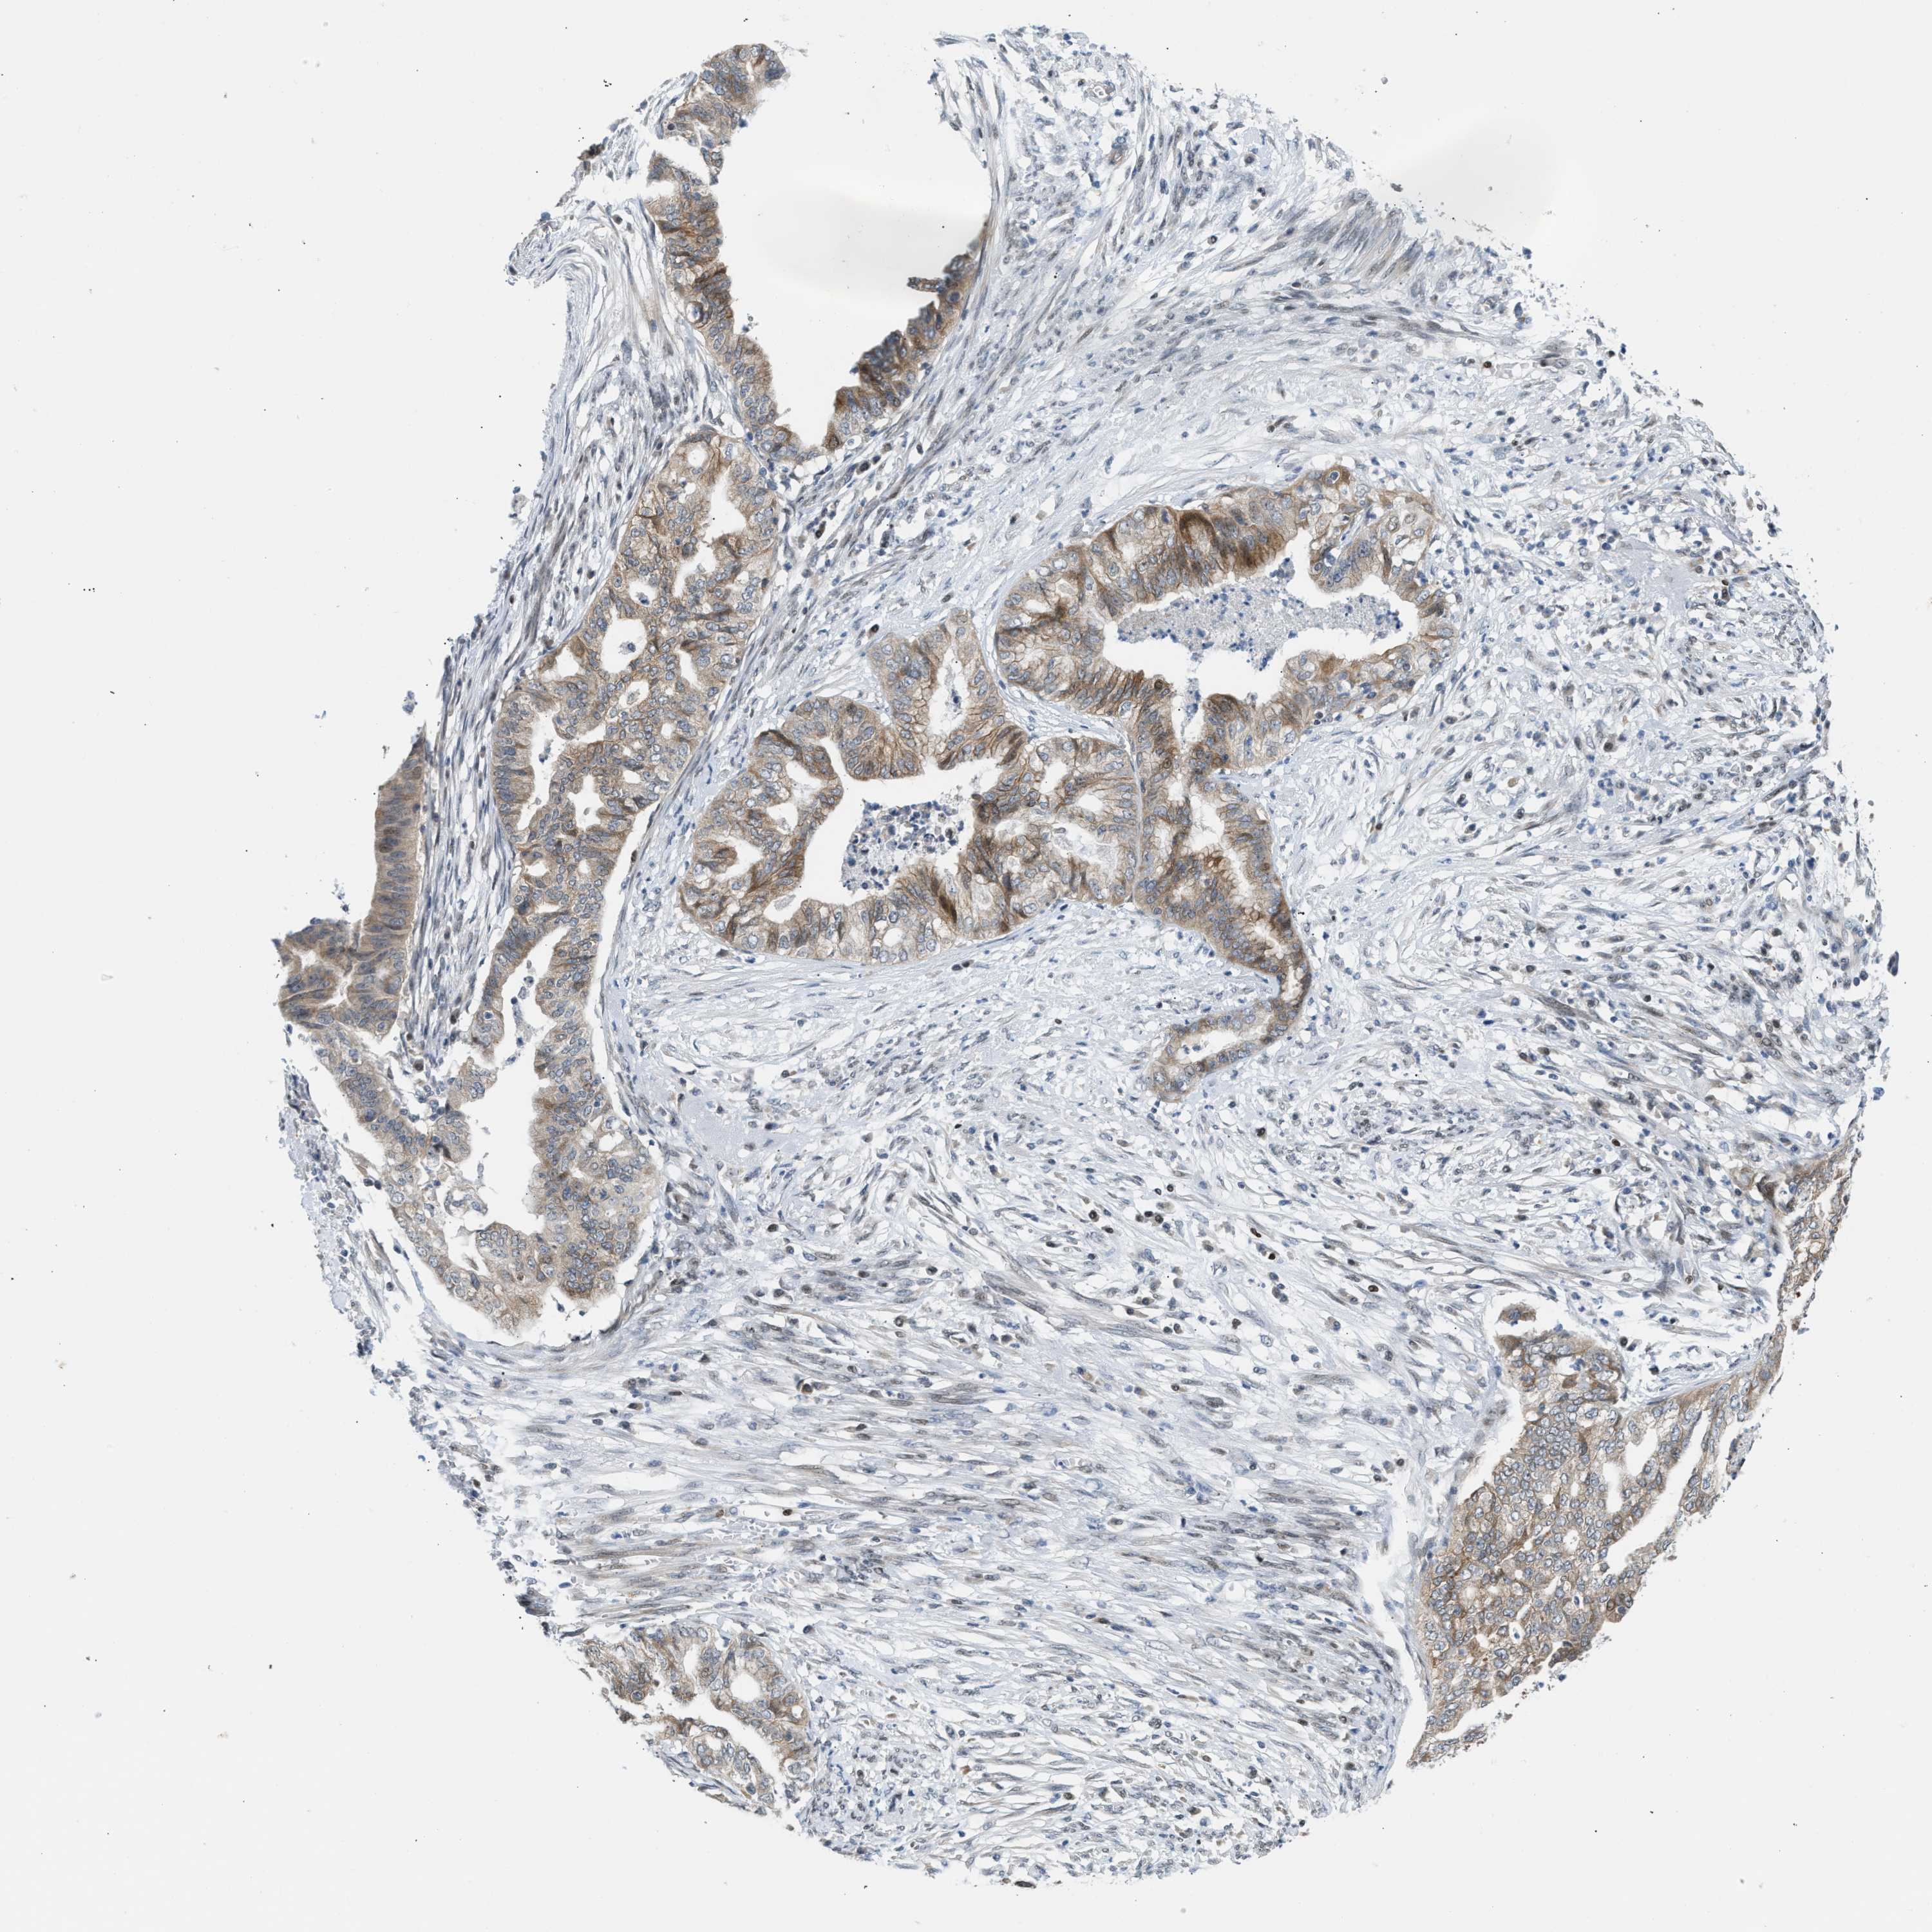

ENDOMETRIAL CANCER - Protein expressioni

A mouse-over function shows sample information and annotation data. Click on an image to view it in a full screen mode. Samples can be filtered based on level of antibody staining by selecting one or several of the following categories: high, medium, low and not detected. The assay and annotation is described here.

Note that samples used for immunohistochemistry by the Human Protein Atlas do not correspond to samples in the TCGA dataset.

Antibody stainingi

Antibody staining in the annotated cell types in the current human tissue is reported as not detected, low, medium, or high, based on conventional immunohistochemistry profiling in selected tissues. This score is based on the combination of the staining intensity and fraction of stained cells.

Each image is clickable and will lead to virtual microscopy that enables deeper exploration of all samples and also displays staining intensity scores, fraction scores and subcellular localization as well as patient and tissue information for each sample.

Antibody CAB020139

Staining

High

Medium

Low

Not detected

Intensity

Strong

Moderate

Weak

Negative

Quantity

>75%

75%-25%

<25%

None

Location

Nuclear

Cytoplasmic/membranous

Cytoplasmic/membranous,nuclear

Adenocarcinoma, NOS